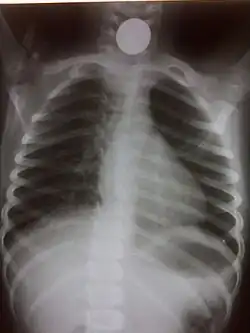

Chest radiograph showing a Venezuelan 25 cent coin lodged in the upper esophagus of a 9-year-old girl. -